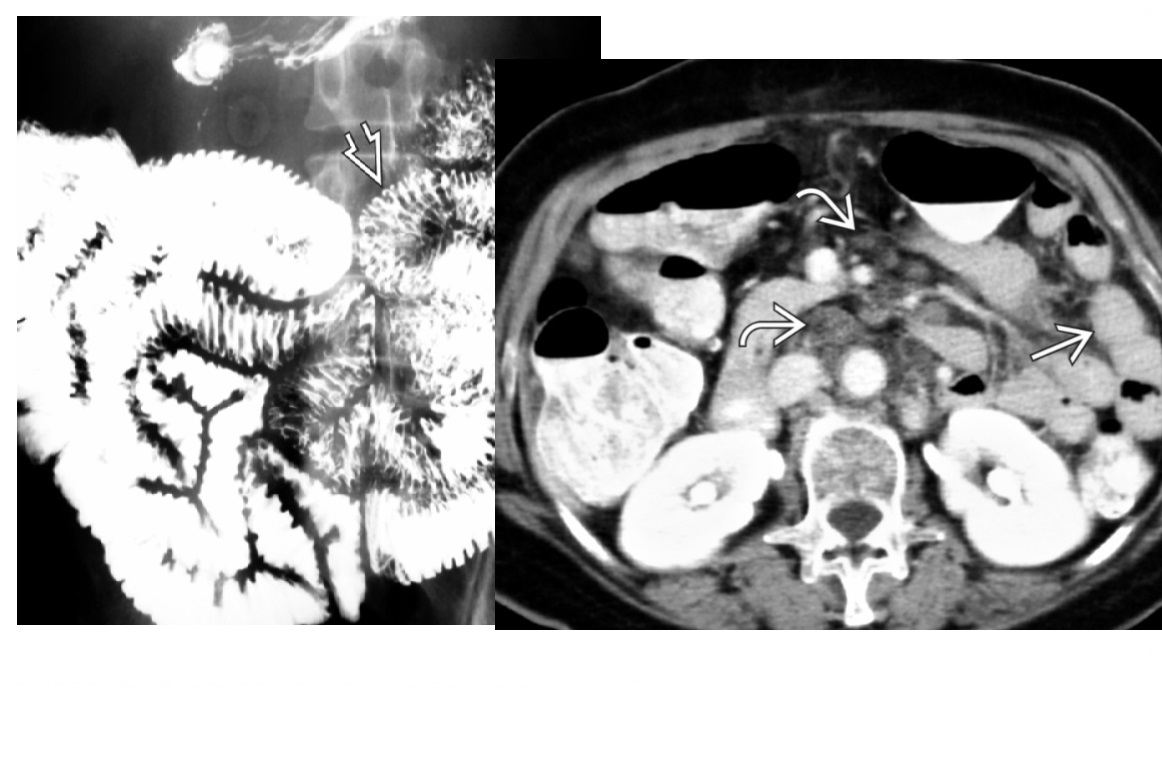

Carcinoid

spiculated mesenteric mass with calcification/ desmoplastic reaction

Tethering of SB loops

90% arise in terminal ileum/appendix

Hyper-vascular liver mets - Carcinoid syndrome

111I- Octreotide scans (1st - highest sensitivity)

or 123I-MIBG (for 10% dont take up octreotide)

for Dx and staging

Big centres use gallium PET

Assocaited with MEN 1 or MEN 2a